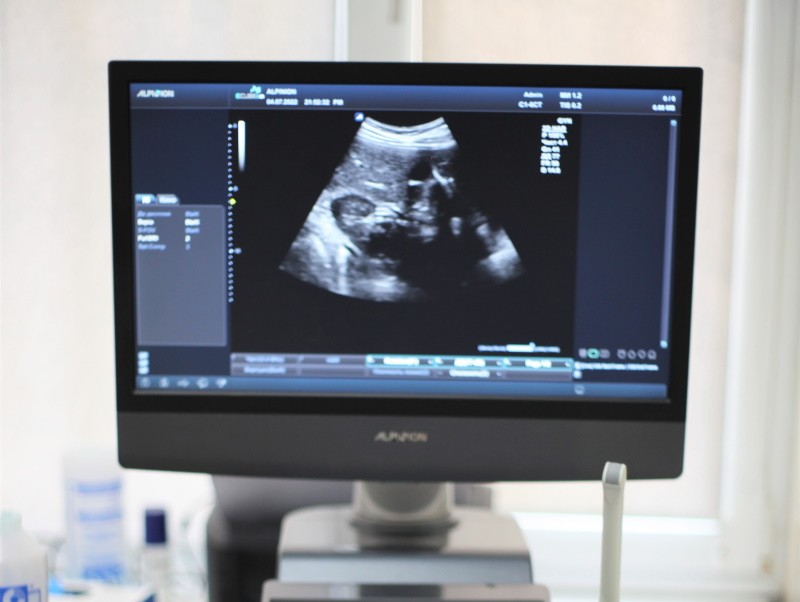

Найчастіші питання про УЗД для вагітних

❓Навіщо потрібно доплер УЗД для вагітних? Ультразвукова доплерографія під час вагітності потрібна для оцінки параметрів кровотоку в судинах плода, матки та пуповини. Порушення кровотоку може призвести до кисневого голодування, порушення нормального розвитку плода і виникнення небезпечних ситуацій. Дослідження призначається гінекологом […]